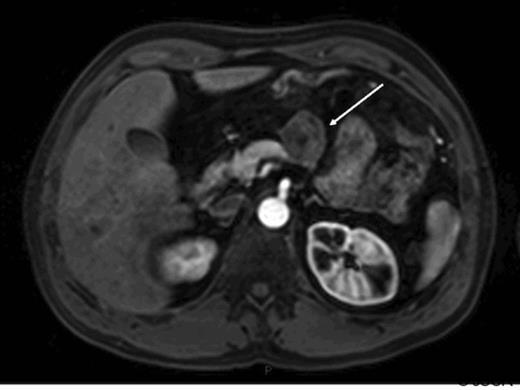

At operation this was a well defined lesion with no evidence of intra-abdominal metastasis. There was no evidence of pancreatitis and the remaining gland appeared normal. Pathology confirmed a single well demarcated mass that histologically was a well-differentiated endocrine tumour. No lymphovascular space invasion was noted and complete excision was achieved with good margins. The tumour measured 39mm, the Ki-67 proliferation index was less than 2% and together with a mitotic count of less than 1 in 10 high powered fields confirmed this was, according to the WHO classification, a well-differentiated (grade 1) endocrine tumour of uncertain behaviour. No cytological atypia or necrosis was identified. The patient made an uneventful post operative recovery however at follow up 6 months later he complained of recurrent sweats and hot flushes. CT scan showed apparent evidence of recurrence of tumour at the site of the previous resection margin in a similar location to the original primary tumour with additional abnormal soft tissue adjacent to the greater curvature of the stomach consistent with local or nodal recurrence. No liver or lung metastases were identified. These findings were confirmed on MRI scan (fig 2).

Arterial phase gadolinium enhanced MRI demonstrating lesion reported as being consistent with recurrent neuroendocrine cancer (arrow).